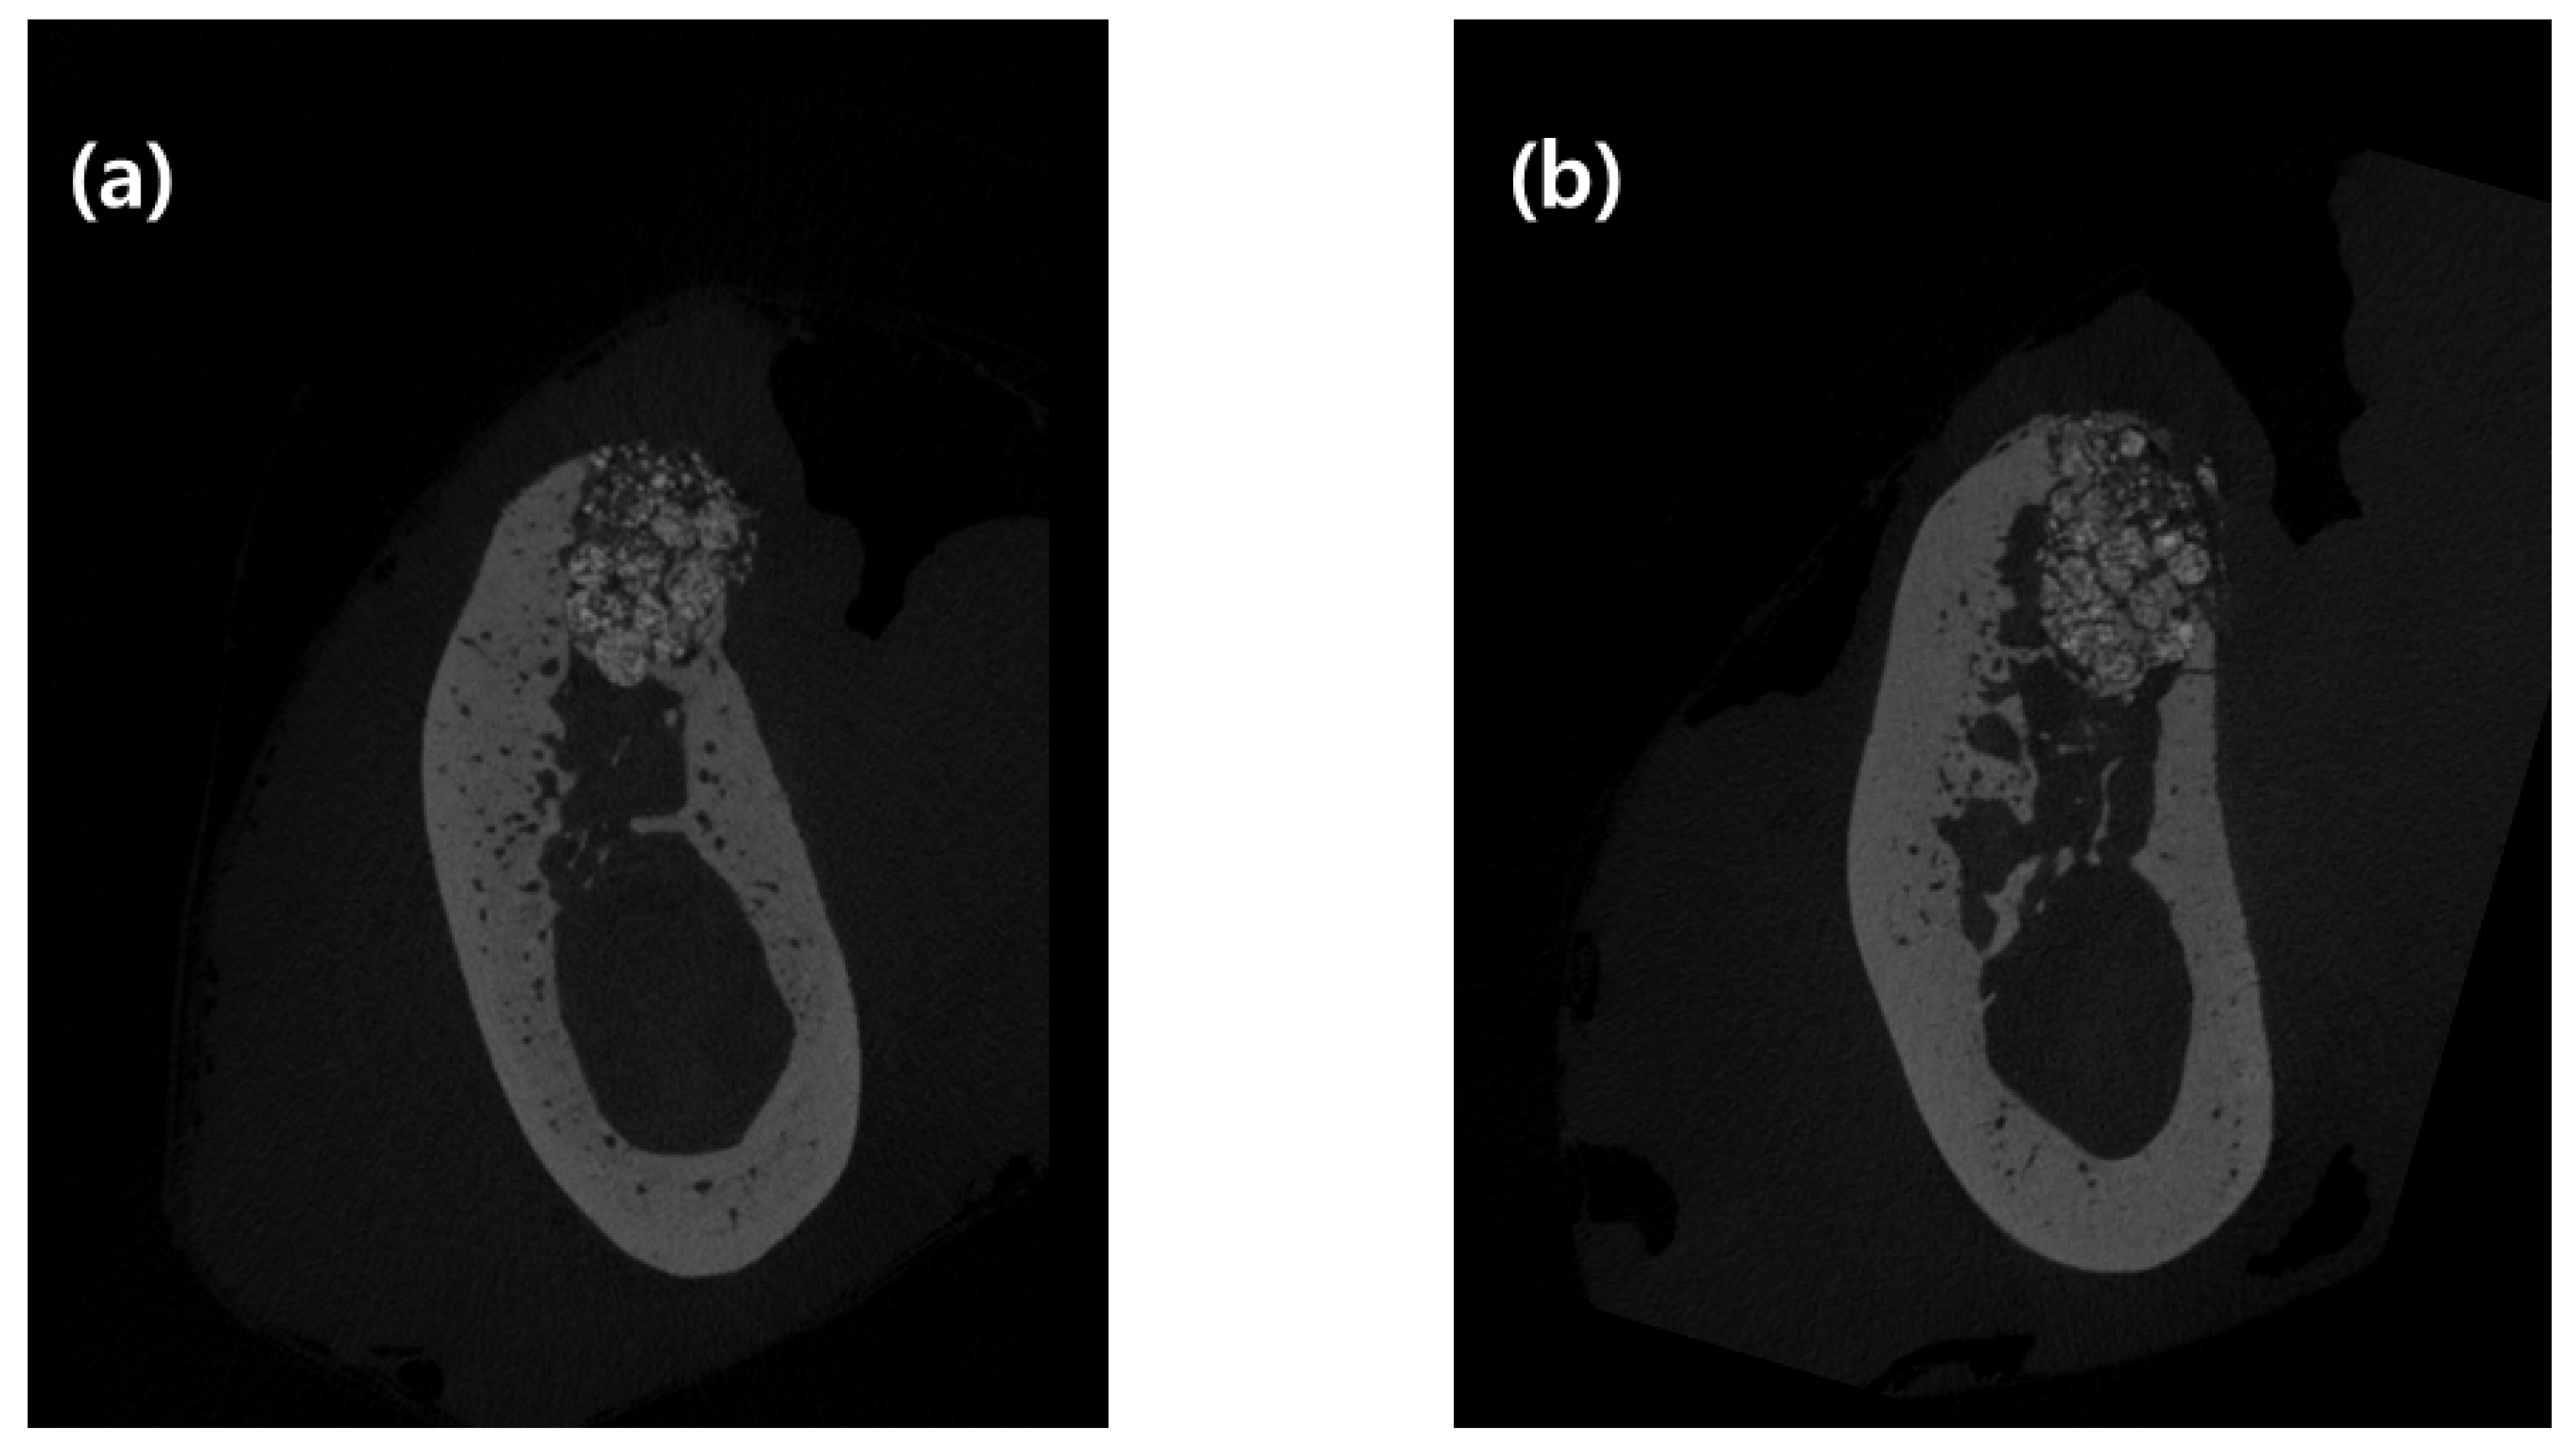

Figure 3.

Buccolingual micro-computed tomography (micro-CT) images of two groups of ridge preservation. (a) Single-layer membrane application and (b) double-layer membrane application. CT images were selected as 3 mm mesial from the experimental septum of tooth.

Vertical distance between the buccal and lingual crests and ridge width at 1, 2, and 4 mm from the lingual alveolar crest (Bw1, Bw2, and Bw4, respectively) using 2D data, and bone morphometric analysis using 3D data, are shown in Table 1. Vertical distance between the buccal and lingual crests was 1.28 ± 0.41 mm in the control group and 0.53 ± 0.37 mm in the test group, which was statistically significant (p = 0.028).

Bw1, Bw2, and Bw4 were 4.46 ± 0.73, 5.88 ± 1.10, and 6.89 ± 0.81 mm in the control group and 4.72 ± 0.83, 5.22 ± 1.35, and 6.25 ± 1.43 mm in the test group, respectively. There was no statistically significant difference between the two groups with respect to radiographic bone width.

The BV/TV value was 56.41% ± 9.91% in the control group and 57.00% ± 10.13% in the test group. BS/TV was 10.69 ± 1.35 in the control group and 10.21 ± 1.98 in the test group. TbPf was 1.14 ± 1.07 in the control group and 0.49 ± 1.51 in the test group. SMI was 0.60 ± 0.54 in the control group and 0.25 ± 0.80 in the test group. There was no statistical difference between the two groups as per three-dimensional micro-CT analyses.

When performing the experiment using micro-CT images, vertical distance between the buccal and lingual crests showed a statistically significant difference between the control and test groups. This difference is attributed to the applied double-layer membrane not being absorbed, and providing support until the soft tissue healed and hard tissue formed.

Bone volume density (BV/TV), BS/BV, TbPf, and SMI were not affected by the number of membrane layers applied. It might be due to their representation of the inside of the extraction socket. However, the number of membranes applied on top of the extraction socket seems to affect the boundary of extraction socket. Therefore, there was no statistically significant difference in BV/TV, BS/BV, TbPf, and SMI. In Bw1, Bw2, and Bw4 as well, there was no difference between the two groups. Given that the vertical distance between buccal and lingual crests was approximately 1 mm in both groups, the bone graft inside the extraction socket, placed 1 mm from the lingual crest, was almost stable. These results are similar to those of previous studies that investigated volumetric changes [22].